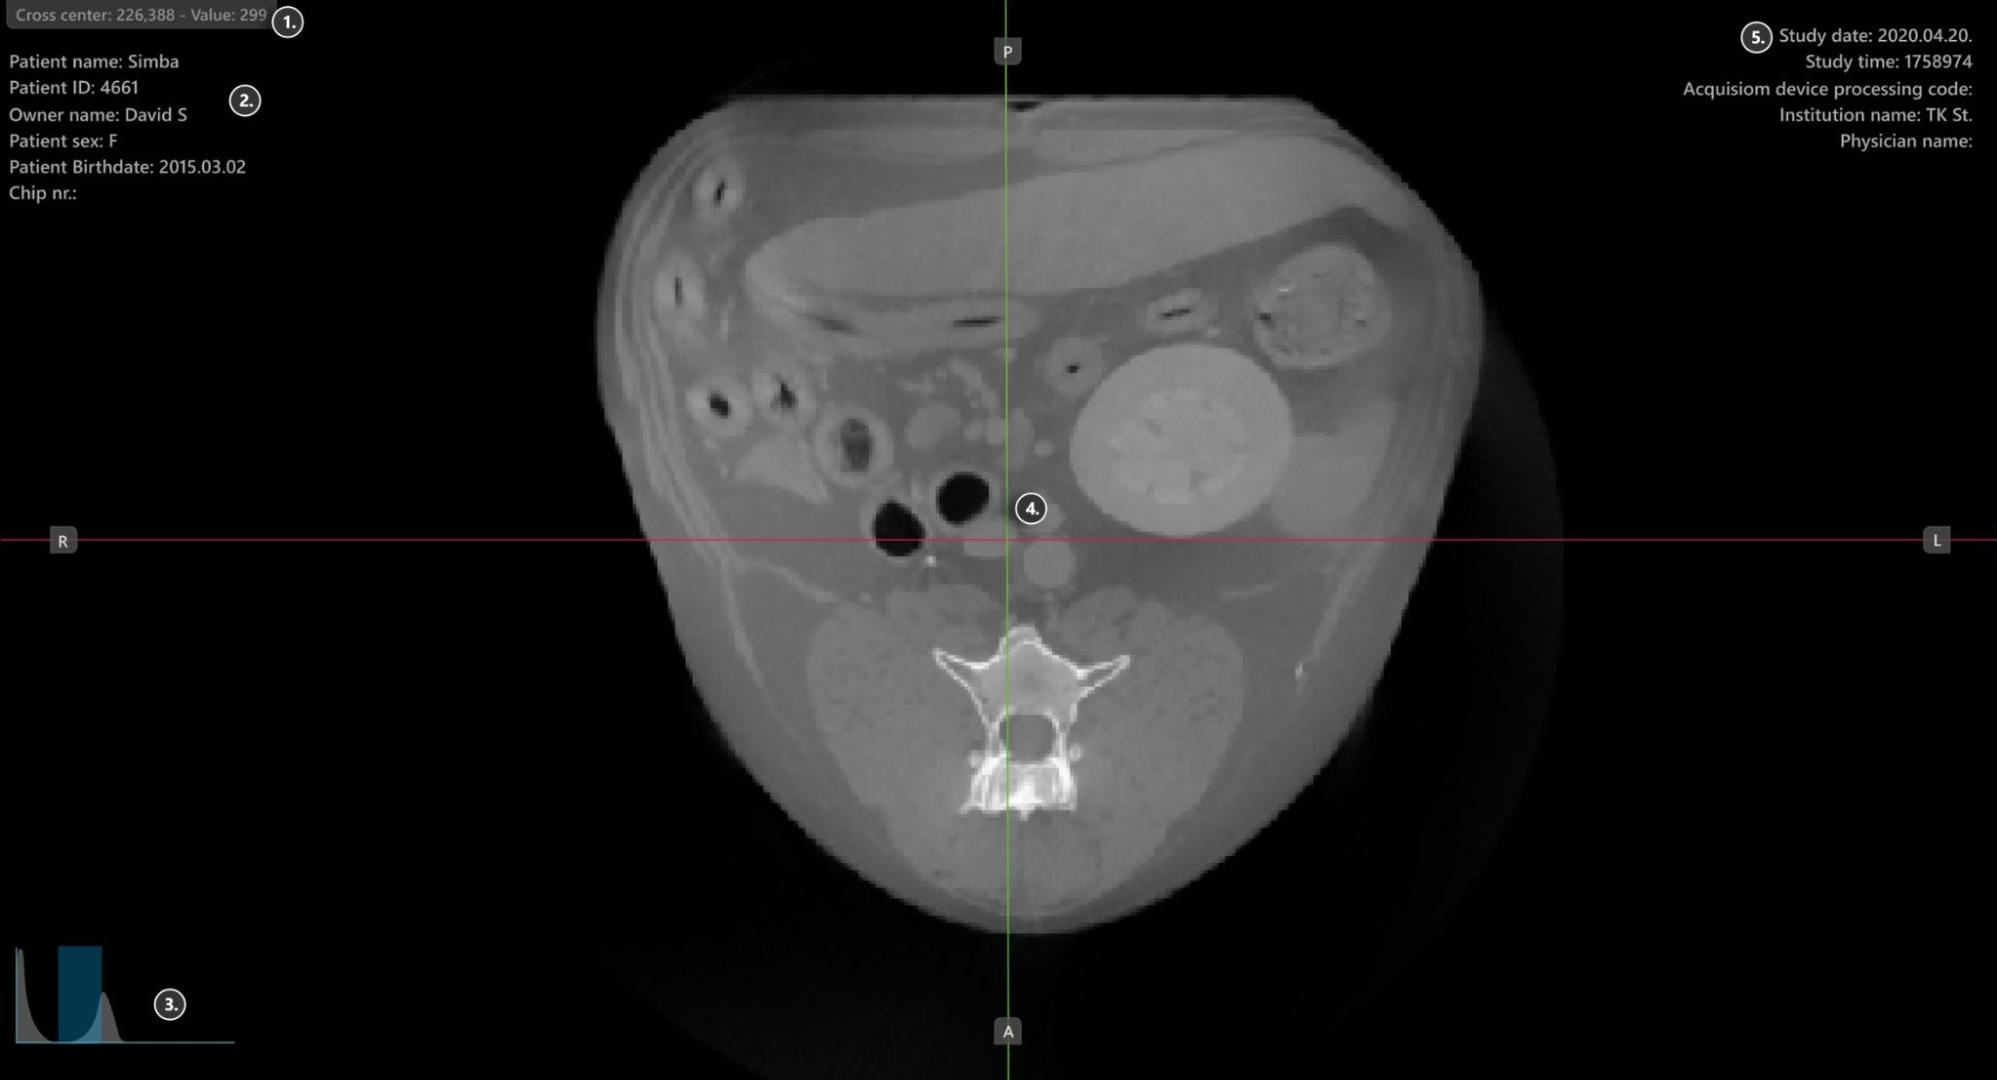

Abschnitte des VisioVIEW CT-Viewers¶

Der VisioVIEW CT-Viewer besteht aus mehreren Abschnitten, die jeweils einem bestimmten Zweck dienen. Im Folgenden finden Sie eine detaillierte Beschreibung jedes Abschnitts.

Viewer-Bereich¶

HU (Hounsfield-Einheit) Pixelwert

Patienteninformationen

Histogramm-Werkzeug für Windowing

Slicer

Studieninformationen